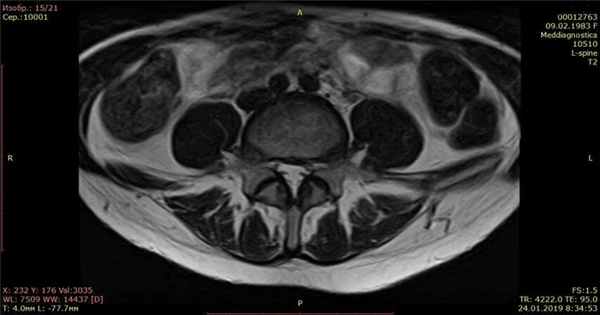

Контрольный МРТ, через 5 месяцев показал полное отсутствие грыжи диска (см. снимки Ирины ниже):

Обратите внимание на даты проведения МРТ в правом нижнем углу. МРТ исследования проведены на одном аппарате 1.5 теслы в клинике «Меддиагностика» в процессе лечения Ирины. МРТ позвоночника позволяет отследить динамику уменьшения грыжи диска.

После лечения назначили лечебную физкультуру для закрепления эффекта. В итоге моя грыжа с 12 мм уменьшилась до 2мм! Я очень рада, что попала в этот центр, где работают профессионалы своего дела, которые ставят людей на ноги и оказывают реальную помощь. Отдельно большое спасибо профессору Гонгальскому Владимиру Владимировичу. Это человек с большой буквы и профессионал своего дела. Рекомендую всем этот центр. Спасибо Вам большое, что Вы есть! С уважением, Ремига Ирина